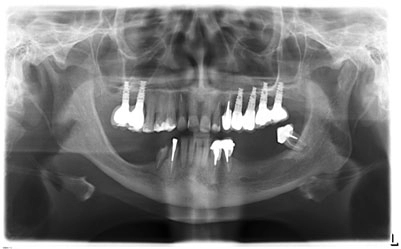

Пациентка C. 48 лет.

Жалобы. При первичном обращении в стоматологическое отделение клиники АО «Медицина» в июне 2018 г. – жалобы на отсутствие зубов.

17, 16, 24, 25, 26, 27 – дентальные имплантаты, покрытые коронками;

37, 36, 35, 45, 46, 47 – отсутствуют;

металлокерамические мостовидные протезы с опорой на 34-33, 43-44 (патологическая подвижность III степени, герметизм нарушен);

23 – под металлокерамической коронкой;

на нижней челюсти – бюгельный протез.